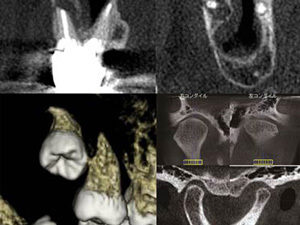

CTを使った安心・安全のインプラント治療

歯を支える顎の骨は、窪みや傾きがあり神経や血管が多く集まっている場所です。とても複雑なので、レントゲンでは骨の影になった神経や血管を確認できないのです。

一方、インプラントや矯正治療では、歯と顎の骨の位置関係、大きさに加えて、神経系や血脈、筋肉や骨の構造を把握しなければなりません。そこで、見えない部分を把握するためのCTが、インプラント治療において欠くことのできない設備となっているのです。

また、治療前だけでなくインプラント施術後の状態もCT撮影をすることで、計画通り行われたインプラント治療を3次元的に確認することができます。

安全性・確実性の面で、CTが患者さまにとって大きな〝安心〟のよりどころになっています。

従来のレントゲンとの違い~立体で把握~

従来のレントゲンでは2次元の平面画像しか得られません。

一方、歯科用CTを用いると3次元の立体画像が得られるので、平面画像ではわからなかった歯やあごの骨の詳細な立体構造や神経の位置などを精度高く把握することができ、より適切な診断・治療が可能になります。

インプラント治療はあごの骨の中にインプラントを埋める治療で、あごの骨がどういう形態になっているか?神経はどの位置にあるか?隣り合う歯との関係性はどうか?などを把握するために立体的に診ることが欠かせません。

そういった立体的な把握に加え、骨質(硬さ)もわかる当院の歯科用CTは他のどの歯科用CTよりもインプラント治療に最適であるといえます。